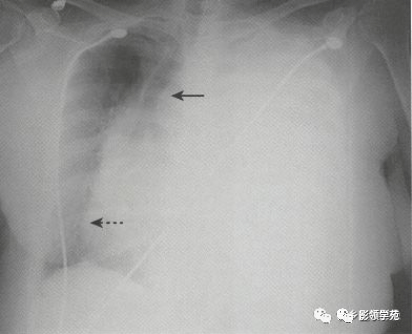

大家看看是膈肌麻痹还是外伤性膈疝?